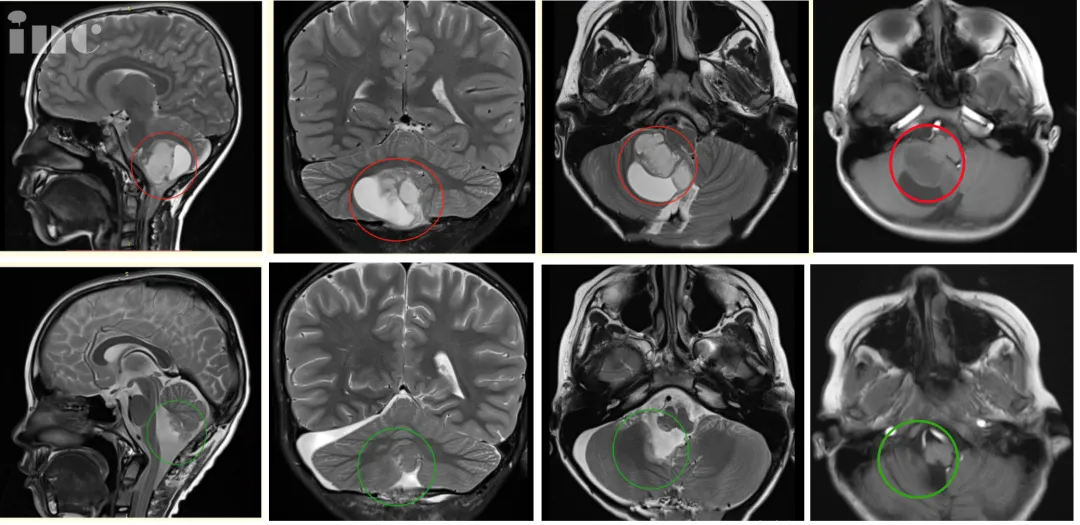

病史回顾:2020年末,6岁的辰辰(化名)在一场小小的交通事故后总是抱怨头晕,核磁共振结果显示“小脑占位”,右侧小脑半球见40mm*37mm大小异常信号,邻近四脑室受压变窄,脑干受压,中线结构局部左移。医生给出诊断,考虑可能是低级别的星形细胞瘤。

手术治疗:巴教授在详细分析辰辰的病情后表示,MR显示非常典型的小脑良性肿瘤,常见的是毛细胞性星形细胞瘤。患儿需要手术。完全切除肿瘤后,这个患儿几乎可以达到从肿瘤中康复。切除率必须达到100%,我将尽一切努力实现这一重要目标。

图4:术前术后影像对比。术后MR复查显示肿瘤全部切除,无残余,脑干得到充分减压,对中脑的挤压/移位压力明显减少,小脑复位。